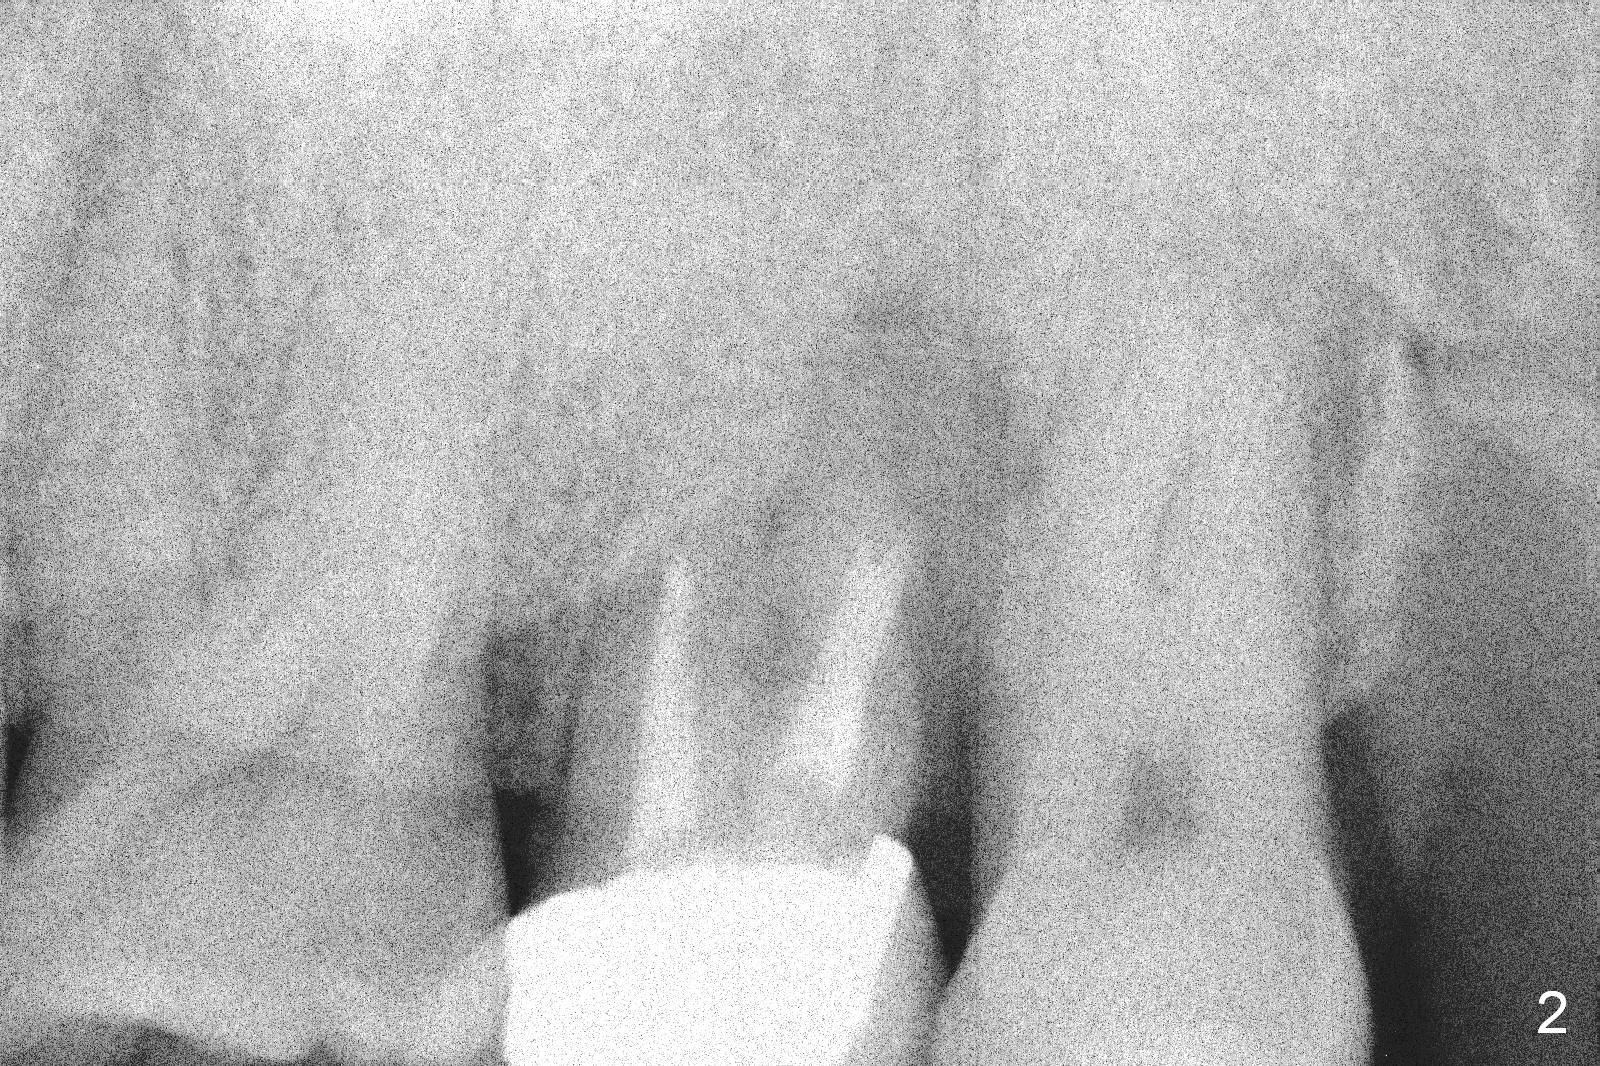

A 47-year-old man (LW) agrees to have the tooth #15 (Fig.1) extracted for implant after 4-year delay (Fig.2).  A 20 mm long implant will have at least 6 mm native bone for stabilization (Fig.3).  Bone density seems to be high.  Use Bicon drill and reamers until 3.5 mm, followed by 5x20 mm Tatum tapered tap and PA.